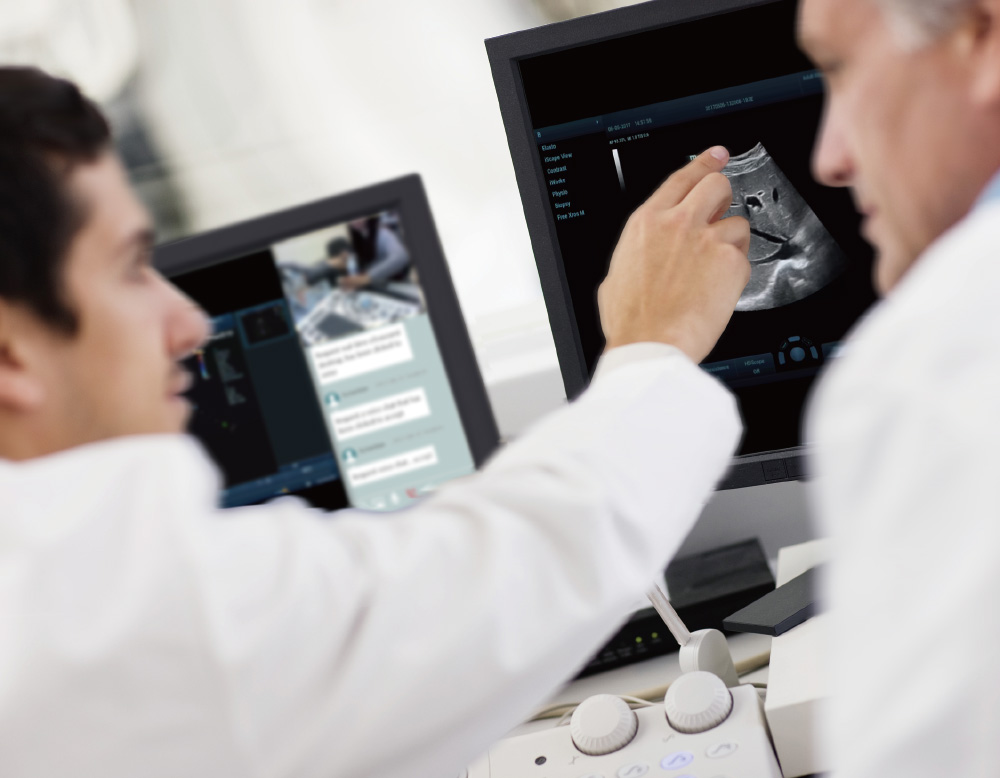

- Ajuda remota: solu??o de colabora??o da Mindray

O TE Air e o Mico+ trabalham juntos realizar o compartilhamento em tempo real de exames de ultrassom, incluindo imagens, ĂĄudio e vĂdeo, para o dispositivo terminal, para orienta??o, treinamento, controle de qualidade, discuss?es de casos e muito mais

Comunica??o em tempo real

Compartilhamento com um clique